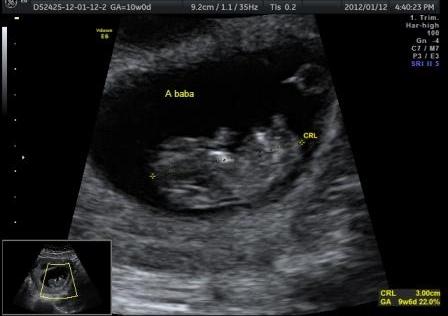

Én ma voltam UH-on és már 15,3 mm-es a drágaságunk.